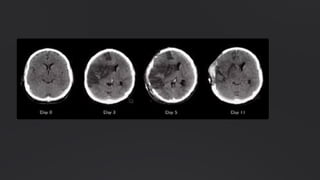

Necrose Liquefativa

Observada em infecções bacterianas ou

fúngicas focais, onde enzimas dos

leucócitos digerem o tecido. Também

ocorre em hipóxia no sistema nervoso

central. As células mortas são

completamente digeridas, formando

uma massa viscosa líquida,

eventualmente removida por fagócitos.